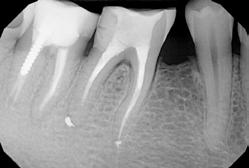

Gyökéramputációt főként a furkáció érintett nagyőrlő fogak ellátása során szoktunk alkalmazni. Derks és mtsai. vizsgálatában a gyökéramputált nagyőrlő fogak közel 80%-a 20 évvel a beavatkozás elvégzését követően is megtartott volt. 1998 októberében egy 39 éves férfi páciens a jobb alsó kvadránsban jelentkező ínyérzékenység miatt kereste fel rendelőnket. A klinikai vizsgálat során jobb alsó első és második nagyőrlő fog között (46–47) nagy kiterjedésű csontveszteséget észleltünk. Ettől eltekintve a teljes fogazat parodontális státusza megfelelőnek bizonyult. A jobb alsó kvadránsban végzett szenzibilitás vizsgálat során arra az eredménye jutottunk, hogy a 46-os fog vélelmezhetően elhalt (10. ábra).

A páciens beleegyezését követően a 46-os fog disztális gyökere, a disztális gyökér felett lévő koronális rész megőrzése mellett rezekcióra került (11. ábra). A rezekciót követően a referáló orvos a 46. és 47. fogak koronáját Ribbond szalag és kompozit segítségével egymáshoz rögzítette. A sebészi beavatkozást követően 22 évvel készült kontrollfelvételen a lézió csontos telődése, kortikális csontállomány kialakulása, valamint a furkáció körüli csontos regeneráció volt megfigyelhető (12. ábra) A károsodott fogak megtartására szolgáló lehetőségek fejlődésének, valamint az implantátumok behelyezésével kapcsolatos rizikófaktorok jobb megértésének köszönhetően ma már más szemmel vizsgáljuk a fogak eltávolításának szükségességét. A kérdéses prognózissal vagy a kis protetikai értékkel rendelkező fogak eltávolítása előtt mindig érdemes felmérni az ezzel elérhető lehetséges előnyök nagyságát. A kemény- és lágyszöveti pótlás lehetőségeinek fejlődésével, a PRF elérhetőségével, a minimálinvazív sebészeti módszerek és az operációs mikroszkópok elterjedésével, valamint a varróanyagok és varrat technikák egyre kifinomultabbá válásával ma már alaposan el kell gondolkodnunk az előtt, hogy egy fogat egy implantátum behelyezése érdekében eltávolítsunk. Mára sokkal kedvezőbb prognózist és sokkal nagyobb sikerességet tudunk elérni a korábban menthetetlennek gondolt fogak kezelése során.